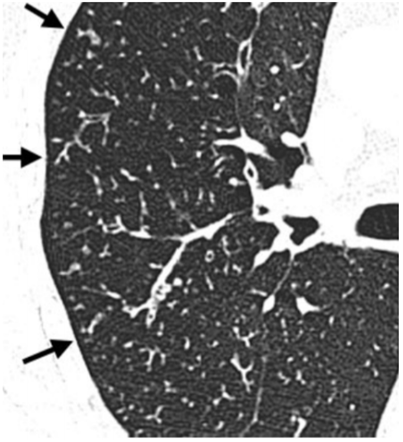

Mulher de 45 anos, sem história pessoal de câncer, foi submetida a exame de ressonância magnética do abdome superior com contraste venoso hepatoespecífico após achado de nódulo hepático incidental em ultrassonografia. Nas sequências pré-contraste, o nódulo apresentava discreto baixo sinal na ponderação T1 e discreto alto sinal na ponderação T2, ambas com supressão de gordura. Abaixo temos imagens nas sequências T1 em fase, T1 fora de fase, T1 pós-contraste (fase arterial) e T1 pós-contraste (fase hepatobiliar). As sequências pós-contraste mostram que o nódulo apresenta intenso realce arterial e hipossinal em relação ao parênquima na fase hepatobiliar.

Diante do exposto acima, analise as afirmativas abaixo e assinale a alternativa correta.

I. Há queda de sinal na ponderação T1 fora de fase tanto no parênquima hepático como no nódulo do segmento IV hepático em relação à ponderação T1 em fase, sugerindo quantidade significativa de gordura intracelular no parênquima e no nódulo.

II. O nódulo do segmento IV hepático tem características compatíveis com hiperplasia nodular focal.

III. O nódulo do segmento IV hepático tem características compatíveis com adenoma esteatótico.

IV. O meio de contraste hepatoespecífico auxilia no diagnóstico diferencial entre hiperplasia nodular focal e adenoma, uma vez que a hiperplasia nodular focal não capta contraste significativamente ou exibe apenas halo captante na fase hepatobiliar, enquanto o adenoma apresenta realce igual ou maior que o do parênquima hepático na mesma fase.